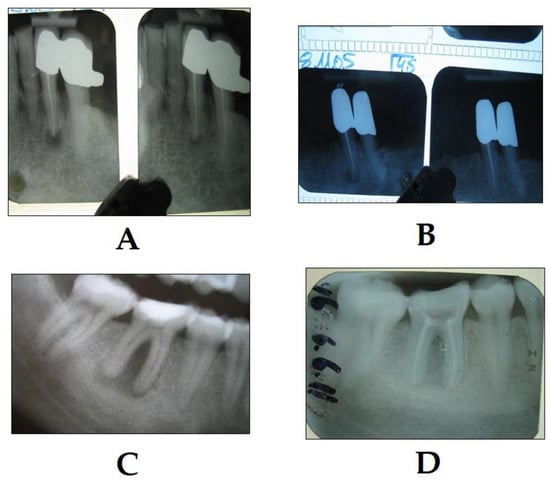

3.2. PDT in Endodontics

- Trindade, A.C.; De Figueiredo, J.A.P.; Steier, L.; Weber, J.B.B. Photodynamic therapy in endodontics: A literature review. Photomed. Laser Surg. 2015, 33, 175–182. [Google Scholar] [CrossRef]

- Okamoto, C.B.; Motta, L.J.; Prates, R.A.; da Mota, A.C.C.; Gonçalves, M.L.L.; Horliana, A.C.R.T.; Mesquita Ferrari, R.A.; Fernandes, K.P.S.; Bussadori, S.K. Antimicrobial Photodynamic Therapy as a Co-adjuvant in Endodontic Treatment of Deciduous Teeth: Case Series. Photochem. Photobiol. 2018, 94, 760–764. [Google Scholar] [CrossRef]

- Fimple, J.L.; Fontana, C.R.; Foschi, F.; Ruggiero, K.; Song, X.; Pagonis, T.C.; Tanner, A.C.R.; Kent, R.; Doukas, A.G.; Stashenko, P.P.; et al. Photodynamic treatment of endodontic polymicrobial infection in vitro. J. Endod. 2008, 34, 728–734. [Google Scholar] [CrossRef]

- Garcez, A.S.; Nuñez, S.C.; Hamblin, M.R.; Ribeiro, M.S. Antimicrobial effects of photodynamic therapy on patients with necrotic pulps and periapical lesion. J. Endod. 2008, 34, 138–142. [Google Scholar] [CrossRef]